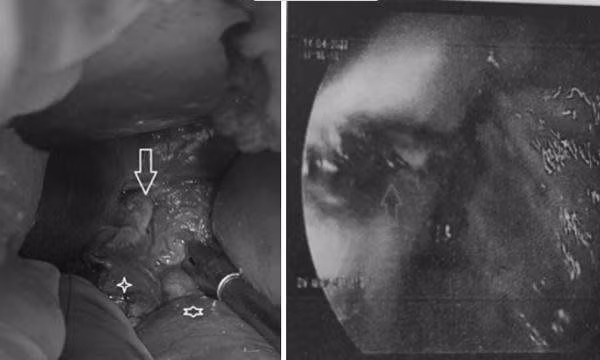

Hình ảnh thực quản trong nội soi dạ dày (bên phải) và lỗ thủng thực quản phát hiện khi phẫu thuật vùng bụng.

Phẫu thuật mở ngực trái ghi nhận góc tâm hoành trái nhiều giả mạc trắng, tụ dịch đục, khối viêm dạng đám quánh ở trung thất sau bọc thực quản kéo dài một đoạn 20cm từ cơ hoành đến ngang rốn phổi trái, tụ mủ đóng kén.

Kết quả thám sát vùng bụng thấy bụng bệnh nhân sạch nhưng quanh thực quản bụng và tâm vị bị bầm. Bơm chất chỉ thị màu, bác sĩ ghi nhận nam bệnh nhân có đường rách thực quản dài 3cm.

Bệnh nhân đã được phẫu thuật khâu lại lỗ thủng thực quản, đắp một phần mạc nối lớn lên đường khâu. Anh cũng được đặt thêm 2 ống dẫn lưu bên cạnh phải - trái thực quản bụng và được mở dạ dày nuôi ăn.